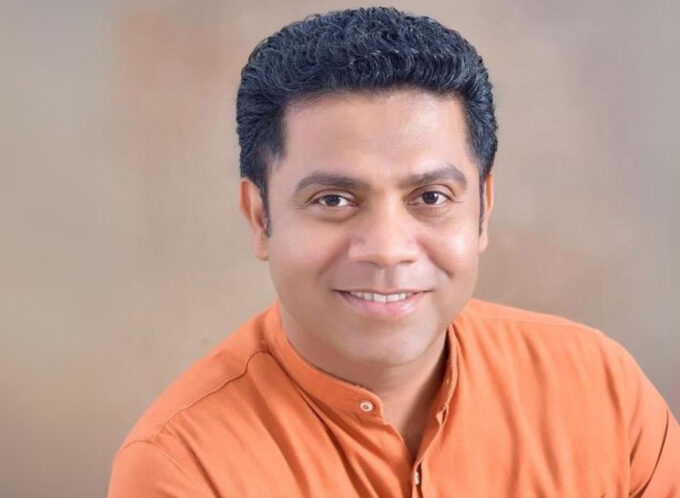

At a recent media briefing, Thoracic Surgeon Dr. Saman Iddamalgoda said lung cancer is now the second most common cancer among men in the country and ranks among the top ten overall based on 2021 data.